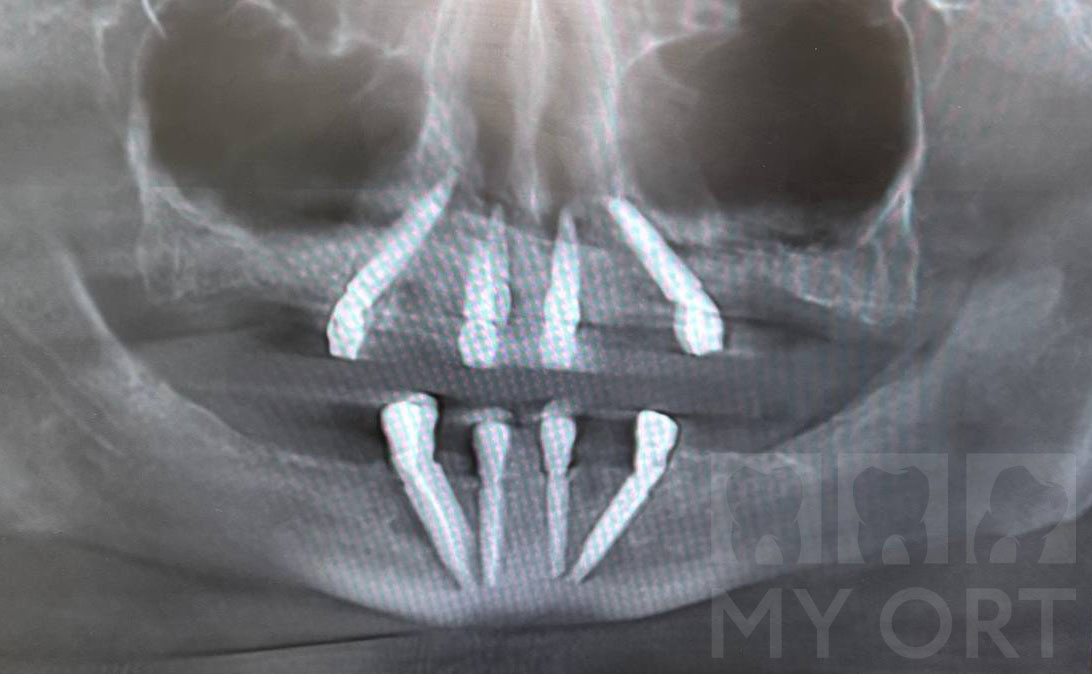

Чтобы создать опору для нового зубного ряда, было принято решение о выполнении транссинусальной имплантации и операции назолифтинга.

Назолифтинг — методика, при которой имплантаты фиксируются в плотных структурах носовой полости.

При недостатке костной ткани в переднем отделе верхней челюсти невозможно установить имплантаты приемлемой длины. При назолифтинге приподнимается слизистая дна носовой полости, создается пространство для установки имплантатов, и их верхушки оказываются под слизистой «в носу». Это обеспечило надёжную фиксацию имплантатов в плотной кости дна носовой полости, позволило увеличить их длину, добиться высокой первичной стабильности и создать условия для немедленной нагрузки и долгосрочной службы конструкции.

Следующим этапом операции было проведение транссинусальной установки имплантатов. В боковых отделах верхней челюсти мембрана гайморовых пазух аккуратно отслаивается и создается место для установки длинных имплантов, которые потом фиксируются в плотных стенках синуса.

Установка длинных имплантатов и фиксация в стенках синуса.

Установка имплантатов. Снимок (КТ)